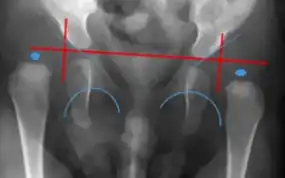

MRI- bilateral dislocation of hips, epiphyseal core (small arrow), and dysplastic acetabulum (large arrow)

X-ray- dislocation of hips